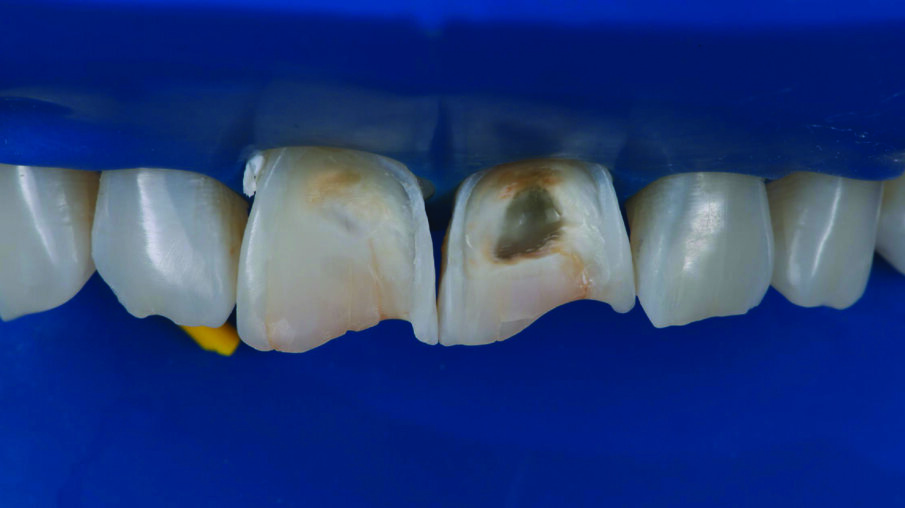

INITIAL SITUATION: Preoperative frontal view of the patient’s teeth, showing severe erosive tooth wear on the vestibular surfaces and incisal edges.

Detailed view of the maxillary incisors. The teeth didn’t show any highly translucent areas, so the use of a single shade/opacity of 3M™ Filtek™ Universal Restorative was selected.